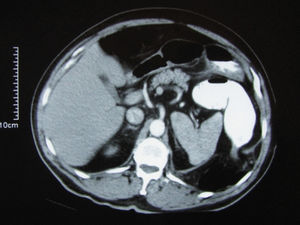

When the patient presented at our hospital, his abdomen was mildly distended and hyperactive bowel sounds were heard. A physical examination revealed muscular rigidity in the left upper quadrant of the patient's abdomen without rebound tenderness or signs of peritoneal irritation. The rectal examination revealed no masses or bleeding. The patient had a temperature of 37.5°C, a heart rate of 100/min, and a blood pressure of 160/90 mmHg. Laboratory analysis revealed an elevated white blood cell count of 19,000/mm3. The other laboratory results were normal. These signs were interpreted as a partial bowel obstruction of unknown origin because the patient was passing stool and flatus. An urgent computerized tomography (CT) scan with oral/rectal and intravenous contrast was performed; the scan revealed a left-sided BH, with a large segment of incarcerated transverse colon (Figures 1–2).

Axial CT scan shows 6-cm opening at the posterior segment of the diaphragm. Transvers colon and surrounding fat tissues enter thorax through the diaphragmatic defect. The entering segment of the colon is narrowed. These changes displace diaphragm, spleen and surrounding fat tissues anteriorly.